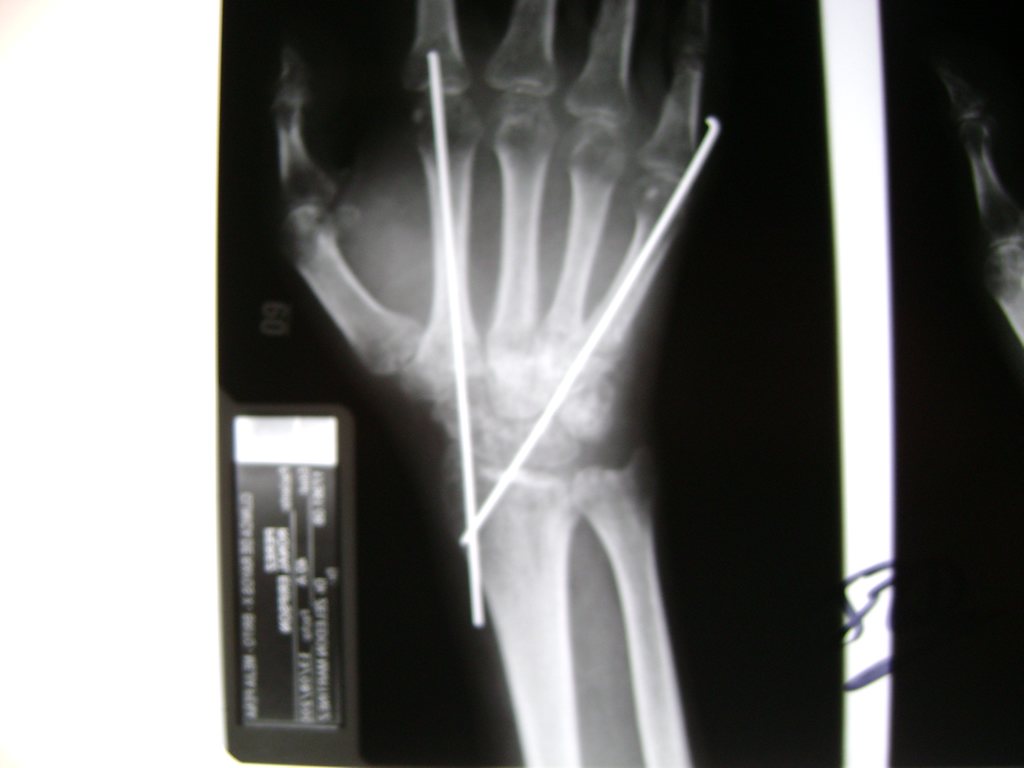

Cirugías de Muñecas

Los procedimientos más comunes en cirugía de la mano son aquellos destinados a reparar traumatismos, incluyendo lesiones de tendones, nervios, vasos sanguíneos, y articulaciones; huesos fracturados; y quemaduras, cortes, y otros daños de la piel.